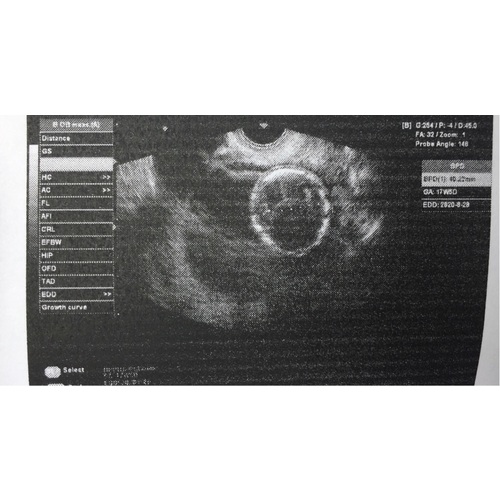

Wat heftig joh zo jong zwanger (je verhaal is wel heel moeilijk leesbaar zonder leestekens en daardoor vrij onduidelijk) Als ik mij goed herinner stond op je echofoto 17+3 weken zwanger? Abortus kan in Nederland tot 24 weken, echter zal een arts het na 22 weken alleen met een medische reden doen. Zonder jou toestemming, doen ze het sowieso niet.

Jeetje wat heftig meis. Ik ben zelf 20 en 29 weken zwanger dat vond ik al jong.... Wat moet je geschrokken zijn toen je de test dee. Ik kan er niet veel meer aan toevoegen wat hier boven staat in nederland kan je tot 24 weken abortus doen maar alleen als jij toestemming geeft, ik heb hier zelf ook mee zitten worstelen en het laat je echt stressen en stress is natuurlijk niet goed voor jou niet en de kleine. Als er op je echo staat dat je 17 weken bent dan klopt dat wel hoor dat is dan je 4de zwangerschaps maand van de 9. Ik vind het heel naar om te lezen dat je vader zo reageert en natuurlijk snap ik dit wel alleen het was beter geweest als er rustig een gesprek aan gegaan werd zonder politie en al dat andere gedoe, Maar goed jou vader mag jou niet dwingen om abortus te doen het is jouw lichaam waar een kindje in groeit niet in die van je vader. Veder wil ik je nog zeggen je bent nog heel jong en een kindje krijgen is echt heel zwaar want ik neem aan dat je nog op school zit? Kies wel wat jij denkt dat goed is voor jou en de kleine want zoon babytje gaat alle aandacht en zorg nodig hebben en vooral liefde en dat is echt vermoeiend op jouw leeftijd. Denk hierbij aan om de 3 uur voeden ook snachts en dat soort dingentjes. Ik hoop dat je hier wat mee kan, ik zeg dit niet allemaal omdat je jong bent maar ik heb het vaker gezien bij jongen meiden daarnaast heb ik zelf op 16 jarige leeftijd een miskraam gehad en dat heeft mij echt in een depressie gebracht nu jaren veder en alles gaat gelukkig weer goed. Hoe is de relatie tussen jou en de vader vab het kind? Want ook hij speelt hier een rol in en heeft net zoveel recht om zijn zoon of dochter op te voeden als jij ondanks het leeftijds verschil, jullie zijn hier allebij "schuldig" aan natuurlijk. Niet alleen hij of jij.... Ik kreeg namelijk de schuld volledig op mij van me schoonouders omdat ik een latex allergie heb en niet tegen de pil kan (ik zou een spiraal laten zetten maar bleek al in verwachting) en ik moest van hun ook abortus doen. Niet gedaan want het is uit eindelijk de keus van mij en mijn vriend geweest en ze hebben zich er bij neer gelegd. Ondanks alles hoop ik dat je niet veel last heb van kwaaltjes en wel een beetje kan genieten van je zwangerschap!